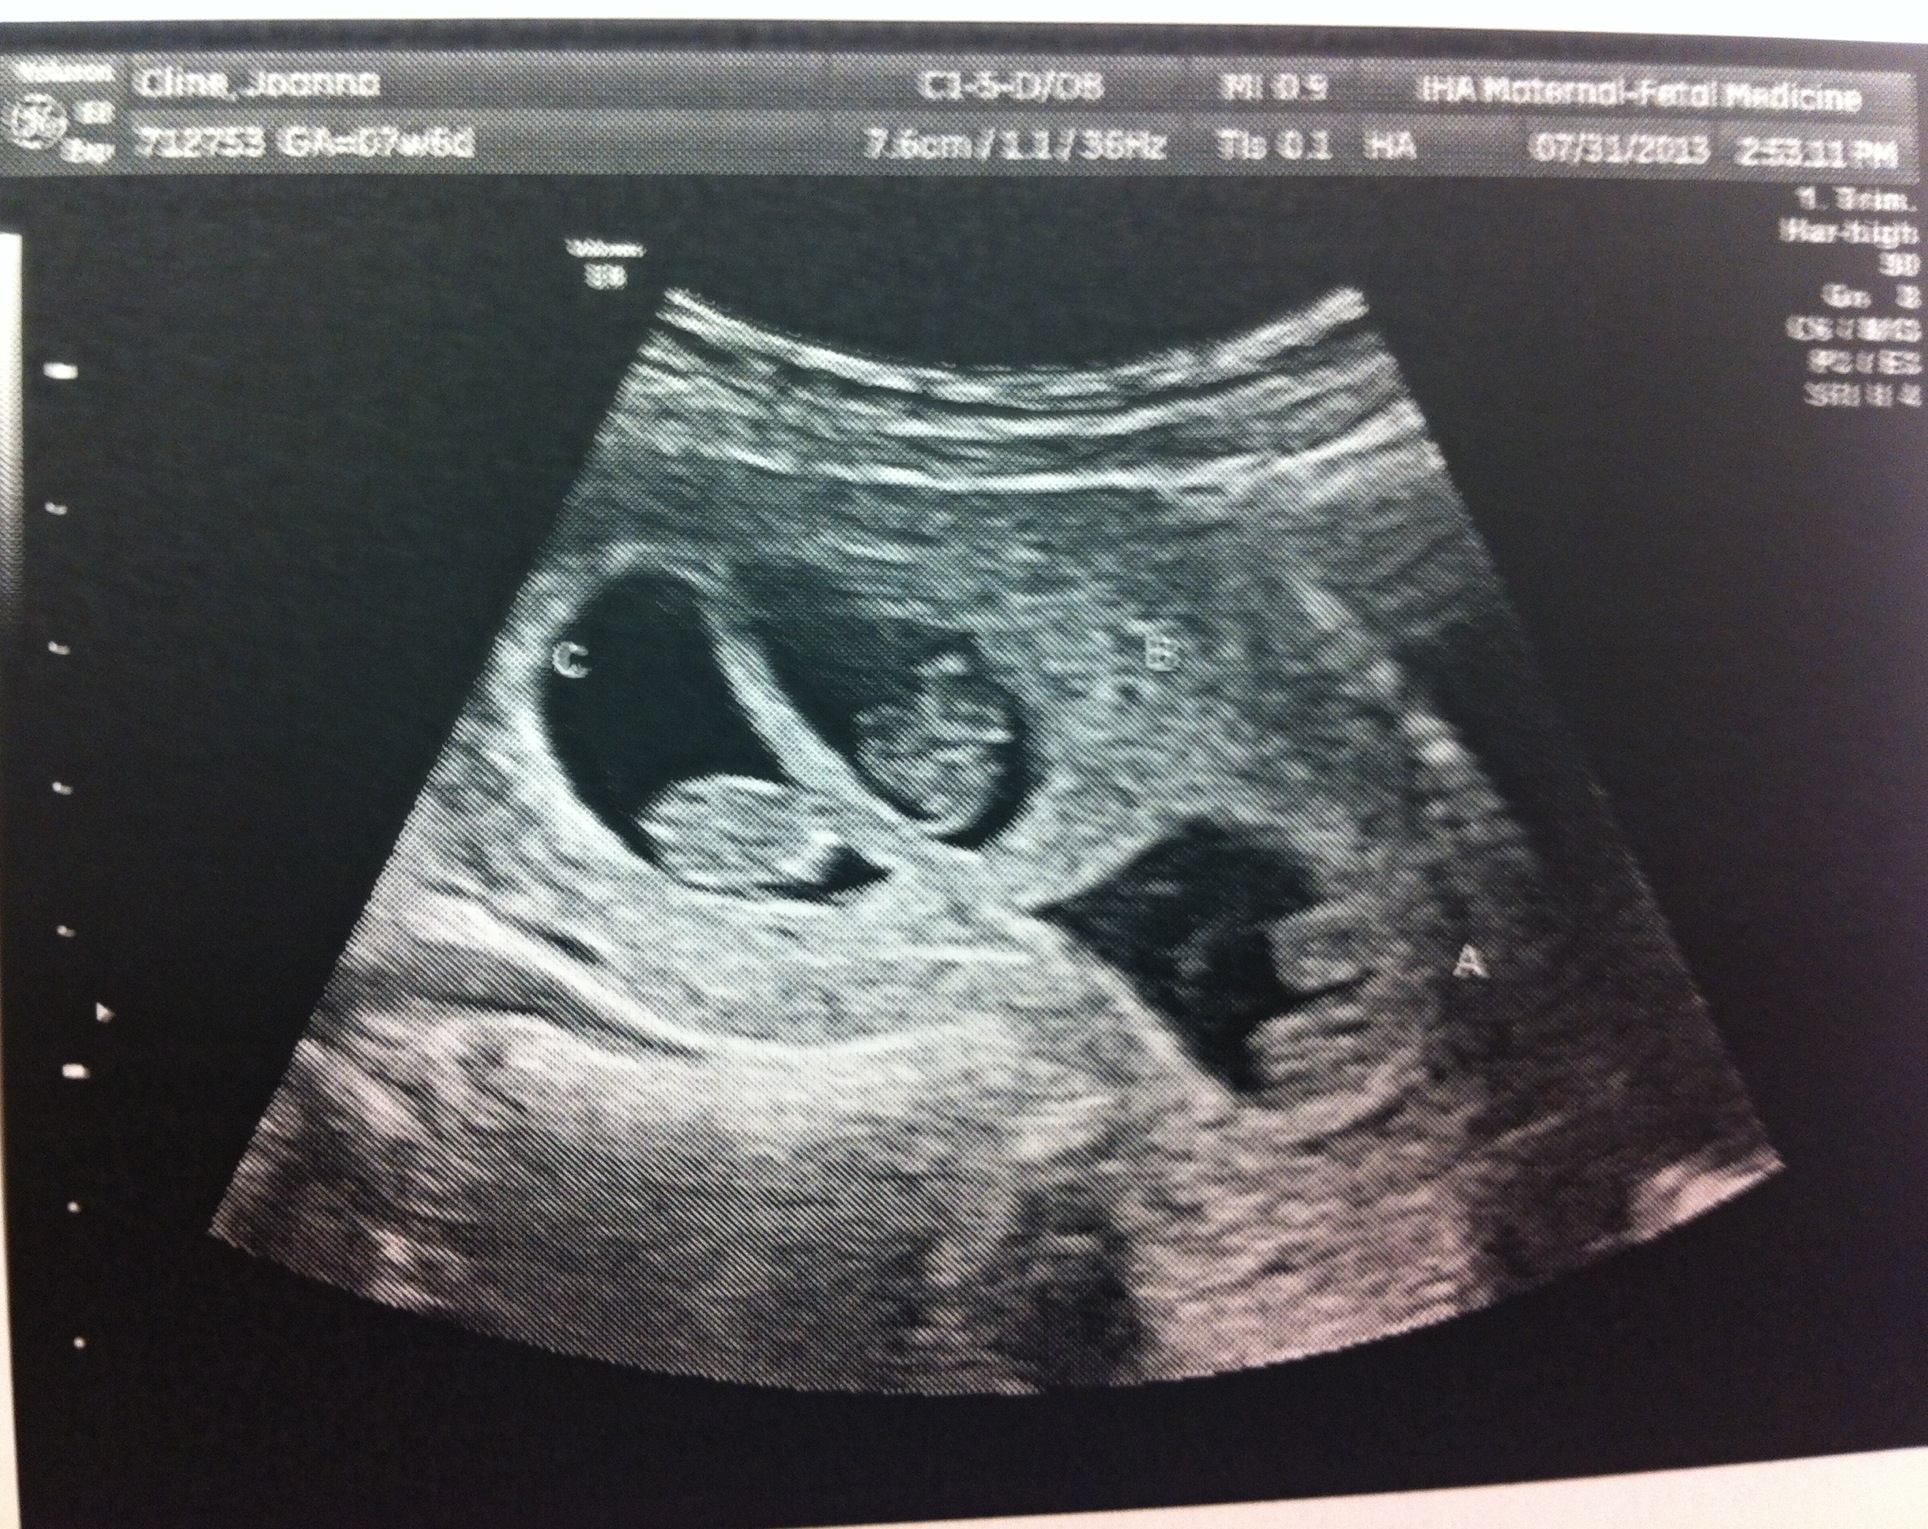

As you know, it’s still early but things look good. Yesterday I saw the specialists who’ll manage my pregnancy. They specialize in high-risk pregnancies and multiples and know how to help us get to term.

Just a reminder to continue to keep the news under wraps. Here’s a photo from yesterday!